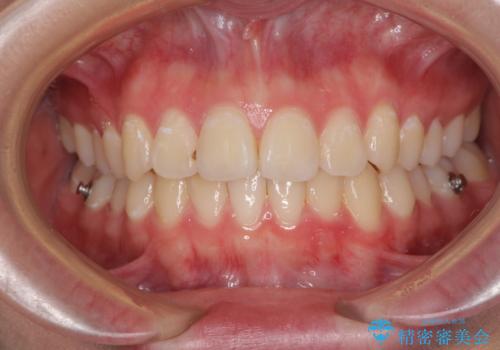

前歯のデコボコを改善 インビザライン矯正

- 1年3ヶ月

ゴムかけをしっかりと行ってもらい、スッキリとした口元に仕上げることができました。